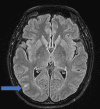

This clinical report discusses the interplay of various pathologies that may present similar clinical manifestations, with uncertainty about the distinct impact of each one of them. The patient is a 43-year-old young Asian female with no known medical conditions. She was 33 weeks pregnant when she was admitted for an urgent c-section because of preeclampsia with HELLP syndrome. While hospitalized, she complained about the visual field's loss. A comprehensive ophthalmological examination revealed a severe concentric visual field defect along with well-reduced visual acuity and impaired color vision. Her OCT revealed a bilateral serous macular detachment related to pre-eclampsia. A brain MRI revealed a microstroke at the temporo-parieto-occipital junction (TPO), although it did not fully account for the severity of the visual field deficit. Despite the macular pathology being resolved, the visual field remained deeply impacted. A thorough and complete investigation yielded negative results, leaving the cause of the patient's deficit unknown. The patient likely had a normal pressure glaucoma. Additionally, multifactorial bilateral microvascular ischemic neuropathy (caused especially by high myopia) has significantly affected her visual field. Furthermore, it is also probable that the patient had genetic neuropathy. Initial genetic testing was negative; however, due to the high suspicion of a genetic component, a retest was conducted, and the results were not conclusive. This case represents a highly unusual case of a profoundly affected visual field with no apparent identified cause. This is a notable example of the potential interaction of various local and systemic pathologies that can manifest with similar clinical presentations.